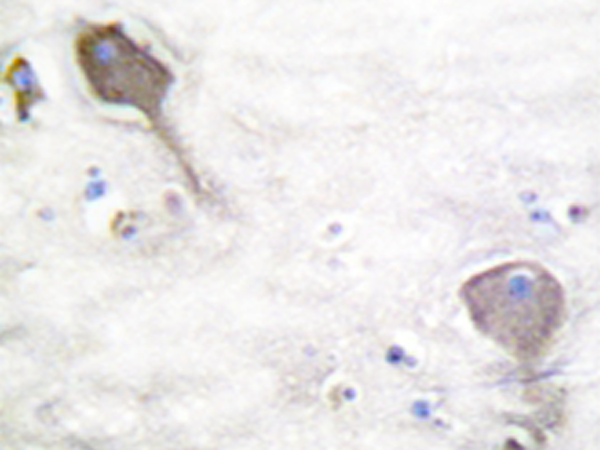

IHC positive control: |

Human brain tissue |

IHC Recommend dilution: |

50-100 |